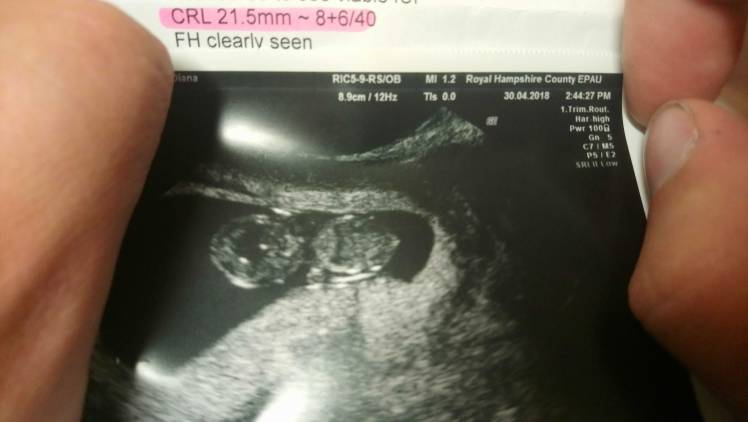

A oto zdjęcie. No dalej nie wierzę.

1525096635074.jpg

Czesc dziewczyny no to i ja sie ujawnie bo juz i tak was podczytuje;) mam 30 lat we wrzesniu jedna strate za soba, w polowie 7 tyg dowiedzialam sie ze zarodek sie nie rozwija, 2 tyg czekalam na poronienie. Biore sulfazalazyne bo po poronieniu pojawily sie objawy reumatologiczne, bylam w szpitalu przebadana wzdluz i wszerz, wszystko ujemne oprocz przeciwcial anty ro. Z nimi trzeba od 16 tyg kontrolowac echo serca plodu. U mnie 8+2chociaz w zeszly czwartek gin mowil ze dalej niz 8 tydz bo dzidzia miala 17 mm i serduszko pieknie bilo:) alw dokladnie nie podal wieku. Termin na 10 grudnia kolejna wozyta 8 maja, bardzo sie boje ale ciesze sie oczywiscie bardzo tez:) biore jeszcze zastrzyki clexane, luteine i prenatal uno i dodatkowy kwas foliowy bo sulfazalazyna jest antagonista kwasu foliowego. 3Mam kciuki za kazda z was, widze ze sporo z was ma aniolki, mam nadzieje ze teraz bedzie pieknie!